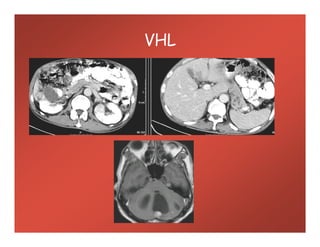

VHL